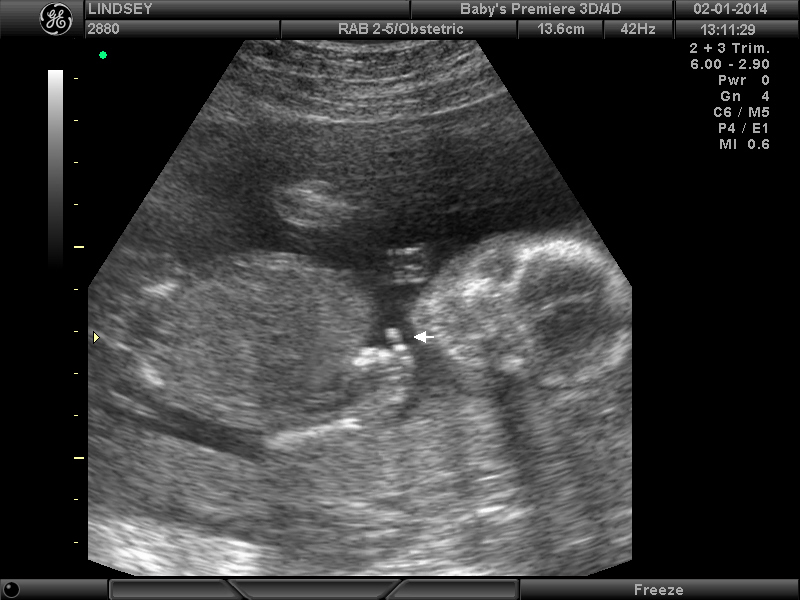

3 Attachment(s)

Help confirming 'girl' ultrasound??

So my Dr. was making me wait a while longer to find out the gender but since I was sooo impatient we went for an elective ultrasound this weekend at 18 weeks. The tech said she was sure it's a girl (yay!!) but I'm so nervous to 100% trust it because I still can't make much sense of the ultrasound myself despite her pointing parts out. (Sorry, new at this! :worry:) It just seems so hard to tell what angle she's seeing everything at. Can anyone ease my my mind and confirm that these are in fact girl parts?? I need to buy something pink!Thanks for any help!! :) :DD: Attachment 16772Attachment 16773Attachment 16774